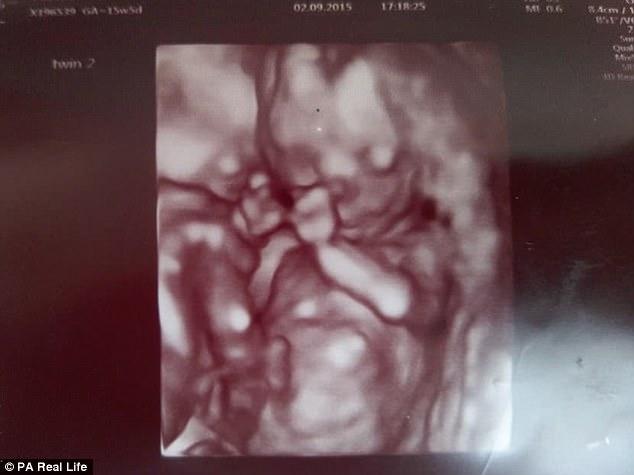

Αλλά τα πάντα άλλαξαν στο υπερηχογράφημα των 12 εβδομάδων, όταν οι γιατροί είπαν στη Vicky και τον Chris πως είδαν ότι τα δίδυμα είχαν μετακινηθεί σε μια στάση που τους έσωσε τη ζωή

“Προς έκπληξή μας, κατά το υπερηχογράφημα των 12 εβδομάδων, είδαμε ότι ήταν αγκαλιασμένοι μεταξύ τους και κρατούσαν ο ένας το χέρι του άλλου,” θυμάται η Vicky.

“Κρατούσαν ο ένας τον άλλον ζωντανό, παραμένοντας στάσιμοι, κι έτσι οι ομφάλιοι λώροι τους δεν μπερδεύτηκαν.”

Όμως, στο υπερηχογράφημα των 12 εβδομάδων, το ζευγάρι είδε κάτι μαγικό – τα αγόρια τους αγκαλιάζονταν και κρατούσαν ο ένας το χέρι του άλλου. «Με το να κάθονται σε αυτή τη στάση δεν μπερδεύονταν οι ομφάλιοι λώροι τους», είπε η Vicky.